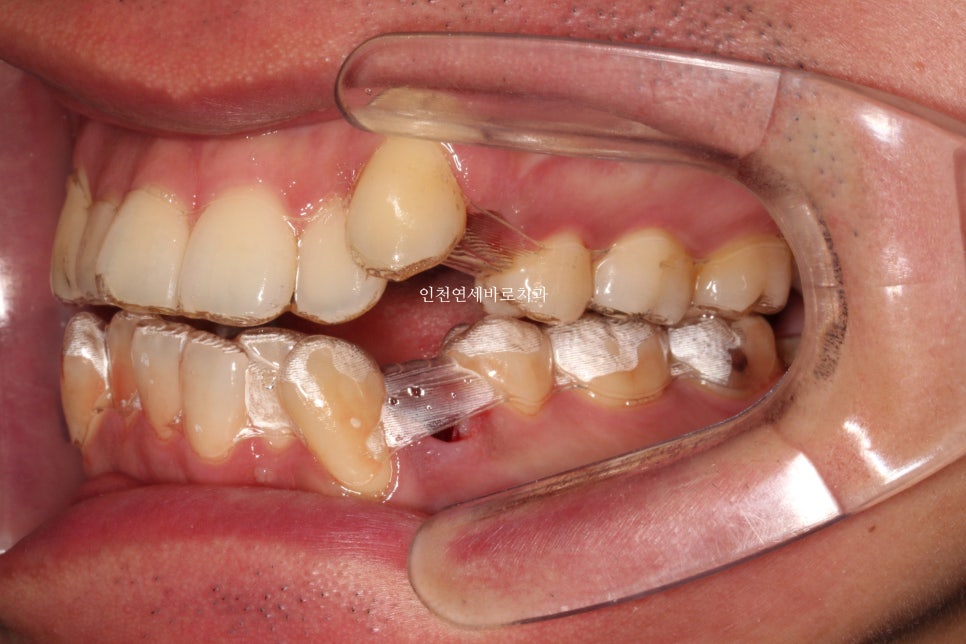

약 1년 4개월이 지난 모습입니다.

첫번째 세트가 마무리 되었고, 원래의 계획이라면 마무리도 가능한 시점입니다.

하지만 중심선과 교합 등 아주 미세한 부분들이 아쉬워 재제작을 권했고, 환자분이 수락해주셨습니다.

재제작 진행.

결국 2년이라는 시간이 지나고 교정이 마무리 되었습니다. (장치 제작기간 2달 포함, 처음 한달 + 재제작시 한달)

치아의 배열이 확인됩니다.

비베라를 이용한 유지를 하기로 해서 제작을 기다리고 있습니다.